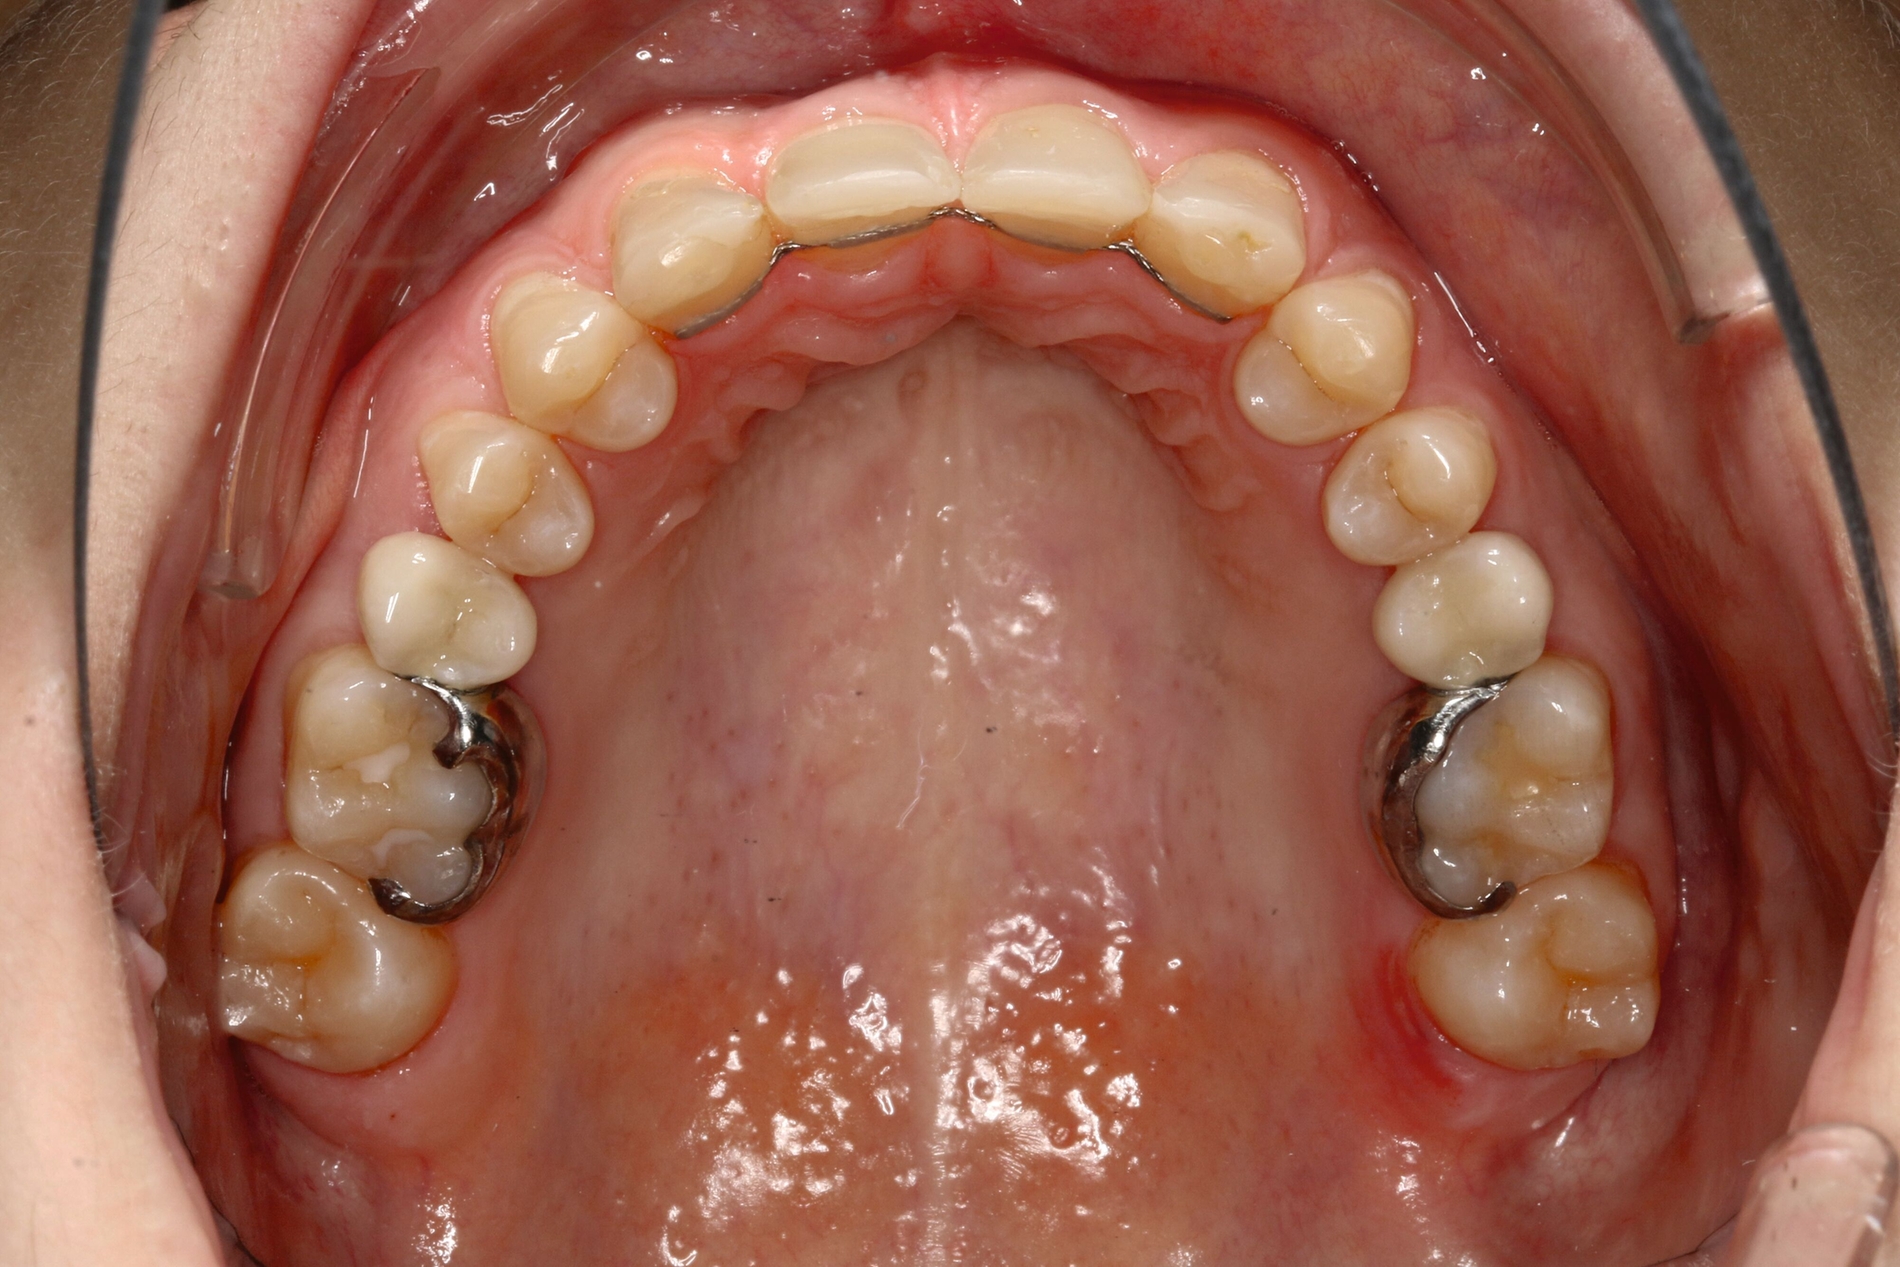

b) im Oberkiefer von okklusal nach Mesialisierung von 13, 14 und 15 sowie 23, 24 und 25 und Lückenöffnung außerhalb der ästhetischen Zone mesial 16 und 26

Im vorliegenden Fall stand der Zahn 23 bereits im Mesialstand bei hoher Lachlinie und tendenziell konkavem Lippenprofil. Bezüglich Morphologie und Farbe waren die Zähne 13 und 23 nicht ausgeprägt eckzahntypisch. Es bestand kein Platzmangel im Gegenkiefer. Die Patientin war bei der Erstdiagnose 12,5 Jahre alt und im Wechselgebiss der zweiten Phase mit atypischer Durchbruchreihenfolge. Es bestand eine geringfügige Klasse II. Der Overjet war vergrößert bei vertikaler Wachstumstendenz, der Overbite war um circa einen Millimeter vergrößert aufgrund der geringfügigen Steilstellung der Oberkiefer-Front. Es bestand der Verdacht auf Nichtanlage der Weisheitszähne, 15 und 25 waren verlagert.

Daher wurde ein Lückenmanagement mit Lückenschluss in der Oberkiefer-Front und Lückenöffnung mesial 16 und 26 außerhalb der ästhetischen Zone angestrebt. Eine implantatprothetische Versorgung kam aufgrund des jungen Alters der Patientin nicht infrage. Die Autotransplantation eines Prämolaren war ebenfalls ausgeschlossen, da kein Engstand und keine Indikation zur Ausgleichsextraktion bestanden.

Eine vollständige Mesialisation der Dentition im ersten und im zweiten Quadranten wurde von der Patientin zur Abkürzung der Behandlungsdauer nicht gewünscht. Ferner bestand der Verdacht auf Nichtanlage von 18 und 28, was bei einer vollständigen Mesialisation des ersten und des zweiten Quadranten zu einer fehlenden Abstützung von 37 und 47 führen kann. Der Rezessus der Kieferhöhle war rechts tief. Alternativ wäre in diesem Fall auch die Lückenöffnung in Regio 12 und 22 denkbar, allerdings dann mit einer prothetischen Restauration in der ästhetischen Zone bei hoher Lachlinie.